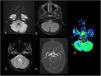

Magnetic resonance imaging at the level of the basal ganglia. A) diffusion sequence, B) FLAIR sequence, C) gradient echo sequence and D) TOF angiography revealing no abnormalities. E) Decreased blood flow in left hemisphere with preservation of left basal ganglia in ASL perfusion sequence.

ASL, arterial spin labelling: FLAIR, fluid-attenuated inversion recovery; TOF, time of flight.

A right-handed girl aged 7 years presented to our hospital with an episode of generalised muscular rigidity with jerking movements in the right upper extremity, disconnection syndrome and relaxation of sphincters. The patient received intravenous benzodiazepines in the emergency department, which achieved resolution of the seizures. Since the patient continued to have a low Glasgow Comma Scale score, aphasia and immobilization of the extremity, the stroke code was activated. A perfusion magnetic resonance imaging scan performed 2 h after onset showed decreased blood flow in the left hemisphere (Fig. 1) and the right cerebellar hemisphere (Fig. 2), with preserved perfusion in the basal ganglia. The electroencephalogram evinced an abundance of epileptiform discharges in the right-side anterior frontotemporal region. Since Todd paralysis was suspected, an intravenous bolus of levetiracetam was administered to the patient, which achieved full resolution of the symptoms in 24 h.

Todd paralysis, also known as post-ictal paralysis, is a condition of unknown aetiology and variable duration1 manifesting with focal weakness after a seizure,2 although, if it involves the dominant side, it can manifest with aphasia in addition to motor impairment,3 as was the case of our patient, and the main differential diagnosis is stroke. Perfusion imaging can evince a reduction in blood flow that does not match a vascular territory, sparing the basal ganglia, and crossed cerebellar diaschisis due to disconnection secondary to the transient metabolic changes in the contralateral corticopontocerebellar pathway.